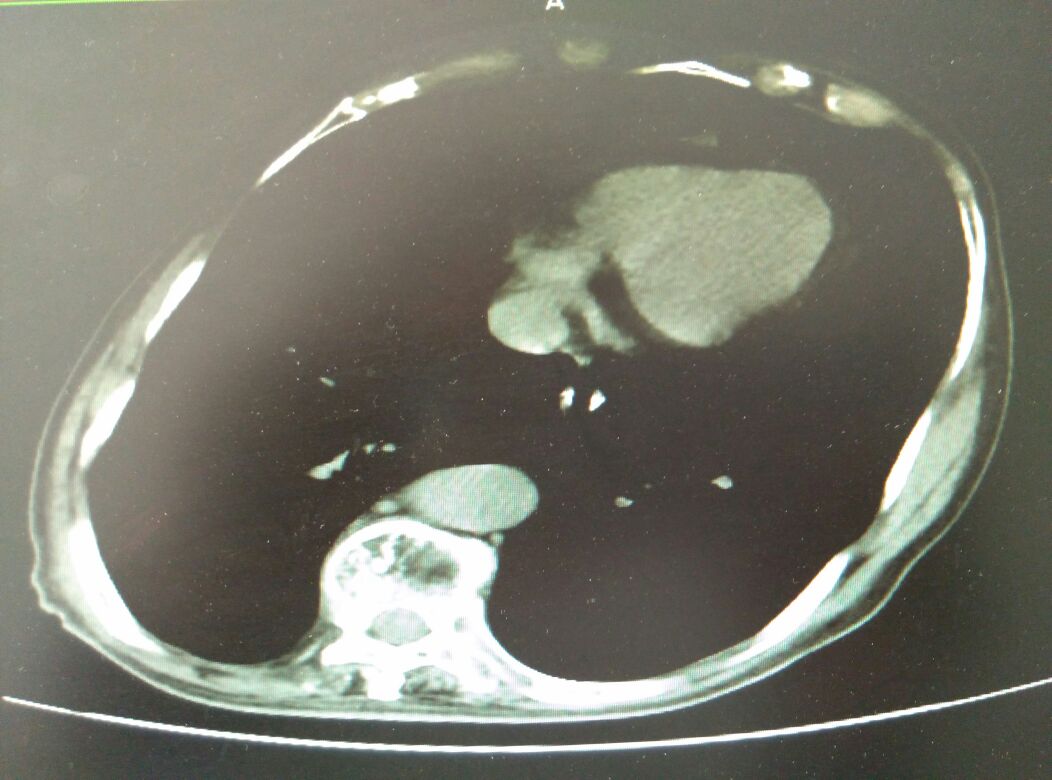

慢阻肺